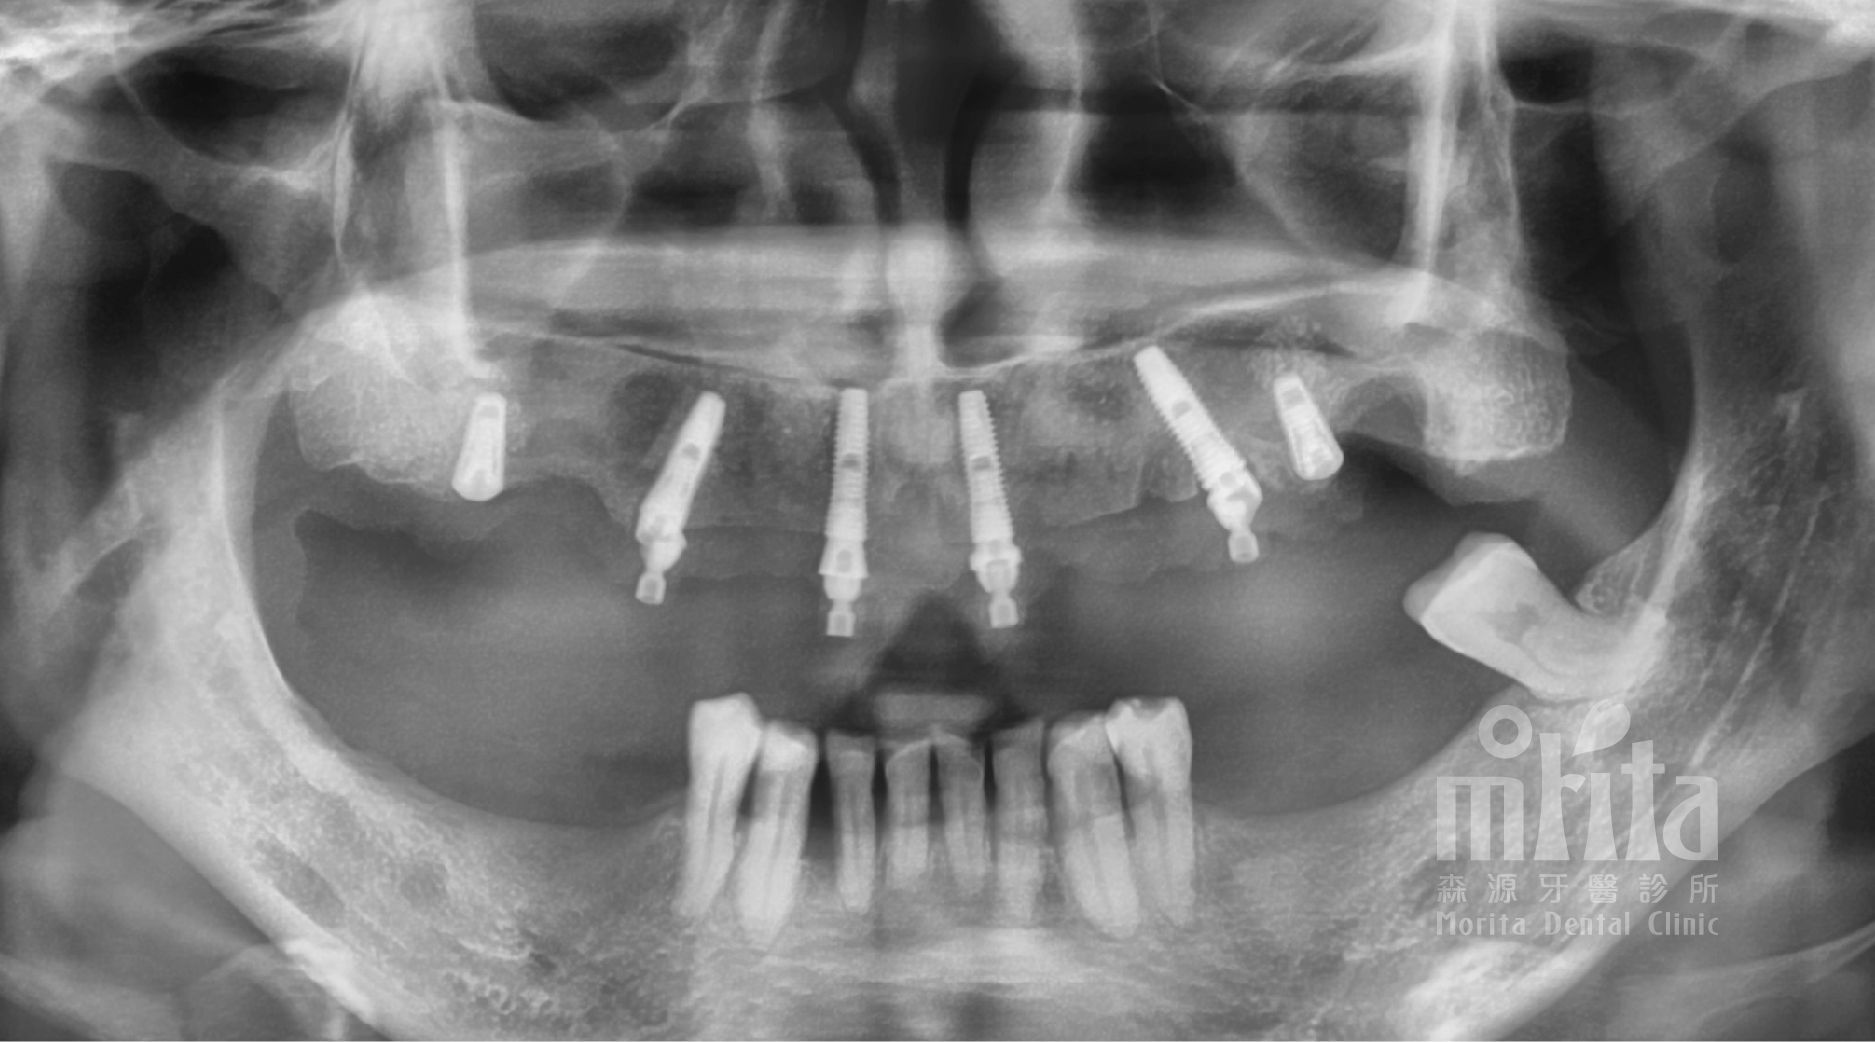

手術後也會再次驗證評估植體的安放設計是否如計畫進行,有沒有需要調整設計的地方。

經由完整的一日假牙療程治療後,馬小姐重拾微笑的自信,以及能夠好好大口吃東西的能力。